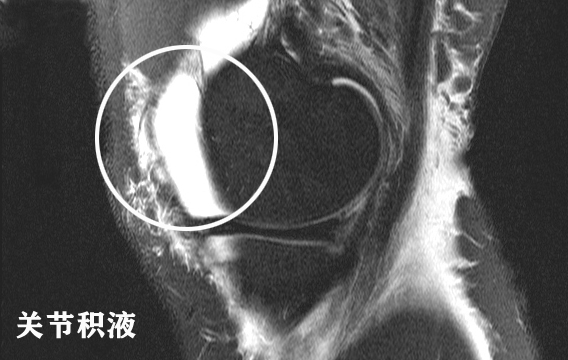

第二,膝关节腔内以及髌上囊少量积液。积液的影像在T2像是高亮的,在片子上会比较扎眼,一眼就能看出来。有积液说明关节内有不明原因的滑膜炎症或者损伤,导致了滑膜的渗出。这个患者的量是少量,所以还可以,问题不是很大。图像一般是这样的: